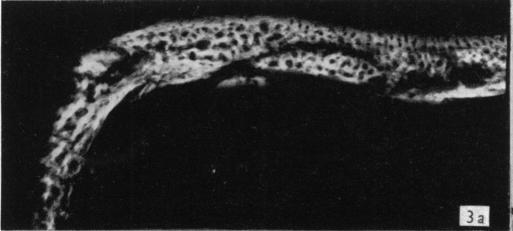

Alizarin as an indicator of bone growth.

J Anat. 1960 Jul;94(Pt 3):432-42.